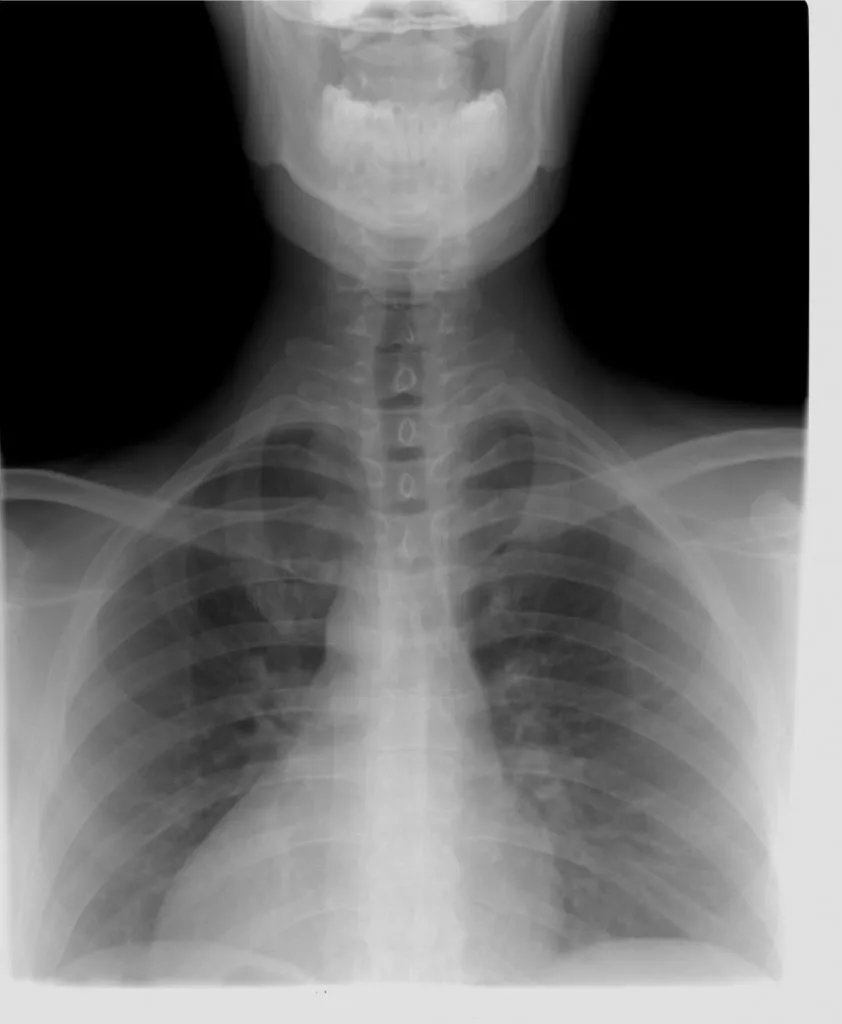

hrct chest

HRCT Chest is also referred to as high-resolution Computed tomography of the chest to visualize the detailed structure of the chest. The scan uses high-quality thin-slice chest images post-processed in a high-spatial-frequency reconstruction algorithm. These help in the easy and early detection of the disorders of the chest.